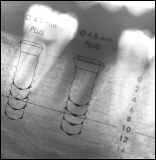

Aktuelles Röntgenbild - radiologische Untersuchung

Ergänzend ist die Auswertung von aktuellen Röntgenbildern (besser nicht älter als 6 Monate) notwendig, falls diese nicht vorliegen, müssen welche angefertigt werden. In der Regel wird eine so genannte Übersichtsaufnahme (OPG = Ortho-Panthomo-Gramm) angefertigt.

Als Ergebnis der Befundaufnahme kann man sagen, wo und wieviel Kieferknochen primär, also im Moment erst einmal, vorhanden ist, um Implantate sicher verankern zu können.